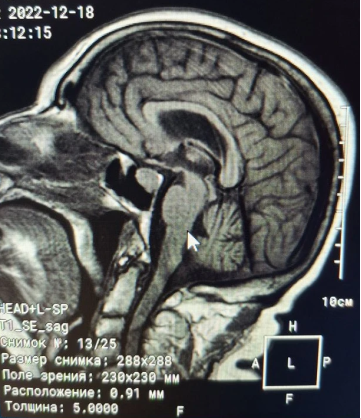

Анамнез заболевания: со слов сына (в сопровождении которого была на приеме), 29.01.2020 пациентка в связи с жалобами на головокружение и слабость самостоятельно прошла МРТ головного мозга (рис. 1, рис. 2, рис. 3).

Рис. 1. МРТ головного мозга (T1 sag sella)

Рис. 2. МРТ головного мозга (T2 Cor)

Рис. 3. Заключение МРТ головного мозга от 29.01.2020